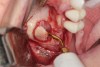

Appropriate rotary burs were used to section the tooth in half in the mesial-distal direction, followed by careful removal of the palatal root half (Figure 17). Next, the remaining labial root was contoured to a thickness of approximately 1.5 mm followed  by removal of the apical third (Figure 18). OD burs were then utilized to densify the bone in the osteotomy via lateral bone displacement (Figure 19). A bone grafting putty (Novabone) was placed into the osteotomy and the implant was then inserted with a primary implant stability reading of 60 Ncm (Figure 20). Typically, mineralized allograft is the preferred choice for grafting between the implant body and facial root.

Fig 17. The root was sectioned mesial-distal, followed by removal of the palatal root half.

Figure 17

Fig 18. Remaining facial root was contoured to a thickness of 1.5 mm.

Figure 18

Fig 19. OD burs were used to create implant osteotomy.

Figure 19